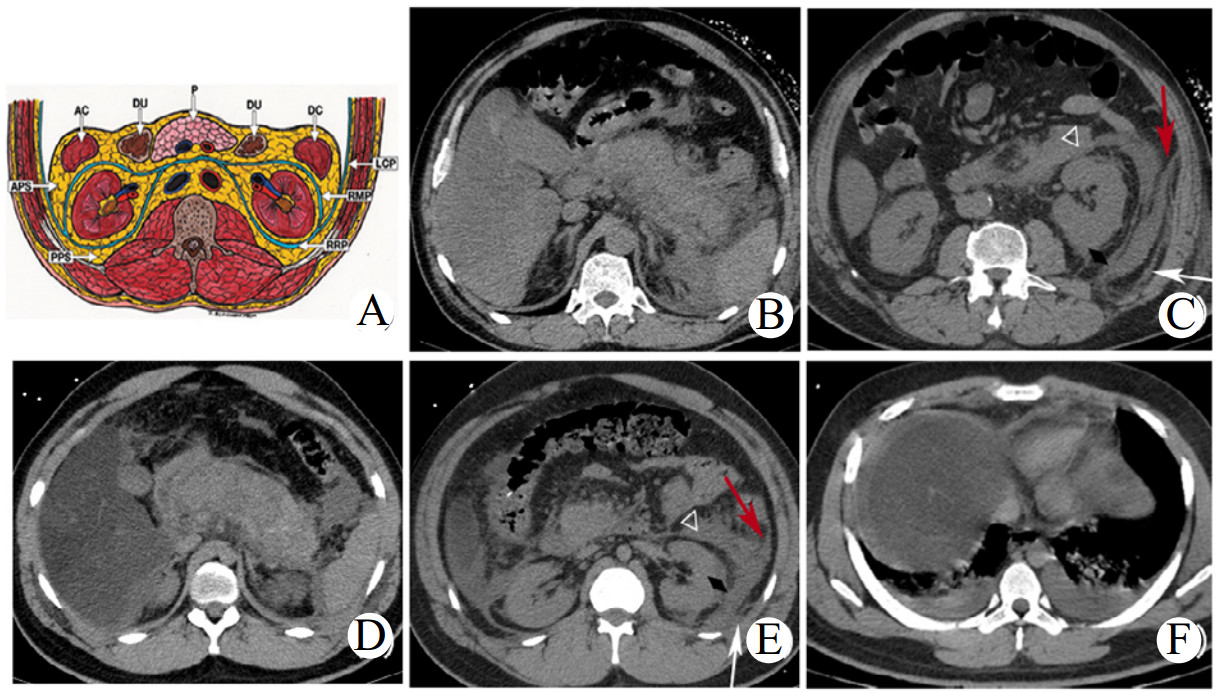

1.2.3 影像学分析所有患者均使用美国GE公司Bright-Speed16层螺旋CT机行轴位腹部平扫检查,主要扫描参数如下:管电压120 kVp,管电流为自动毫安秒,层厚、层间距均为5 mm,扫描速度75 r/min,视野500 mm×500 mm,矩阵512×512。使用东软影像诊断工作站软件(Version 5.5.19071)分析CT原始图像。平扫CT征象由2位经验丰富的影像医师在对其他资料未知的情况下进行独立判读完成,若存在争议,则经协商决定出一致结果。影像征象包括:胸腔积液、腹水、肾旁后间隙(posterior pararenal space,PPS)受累、肠系膜受累、肝/脾CT值减低、十二指肠憩室等。部分CT征象见图 1。1.2.4评分使用MCTSI、Balthazar分级和EPIC评分对所有患者进行评分并记录。(A)腹膜后间隙断层解剖示意图(引自参考文献17)。(B、C)54岁男性SAP患者,腹部CT示胰腺肿胀,边界不清,周围见絮状模糊影;左APS(白色三角形)、左RRP(黑色菱形)、左LCP(红色箭头)见炎性渗出物累及,左PPS(白色箭头)内见条片状模糊影。(D、E、F)27岁男性SAP患者,腹部CT示胰腺肿胀、密度不均,周围见大量渗出,累及左APS(白色三角形)、左RRP(黑色菱形)、左LCP(红色箭头)、左PPS(白色箭头);肝脏密度明显减低,附见两侧胸腔积液、两肺部分不张。缩略词:APS:肾旁前间隙;RMP:肠系膜后平面;RRP:肾后平面;LCP:侧锥筋膜平面;PPS:肾旁后间隙。见图 1。

| 图 1 腹膜后间隙断层解剖图及SAP典型CT征象示意图 Fig 1 Schematic diagram of sectional anatomy of retroperitoneal space and typical CT signs of SAP |